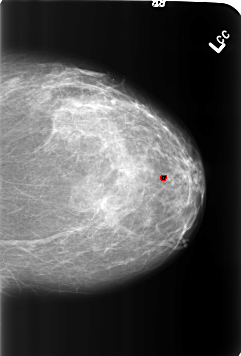

B_3213_1.LEFT_CC

FILE: B_3213_1.LEFT_CC.OVERLAY

TOTAL_ABNORMALITIES 1

ABNORMALITY 1

LESION_TYPE CALCIFICATION TYPE LUCENT_CENTER DISTRIBUTION N/A

ASSESSMENT 2

SUBTLETY 5

PATHOLOGY BENIGN_WITHOUT_CALLBACK

TOTAL_OUTLINES 1

BOUNDARY